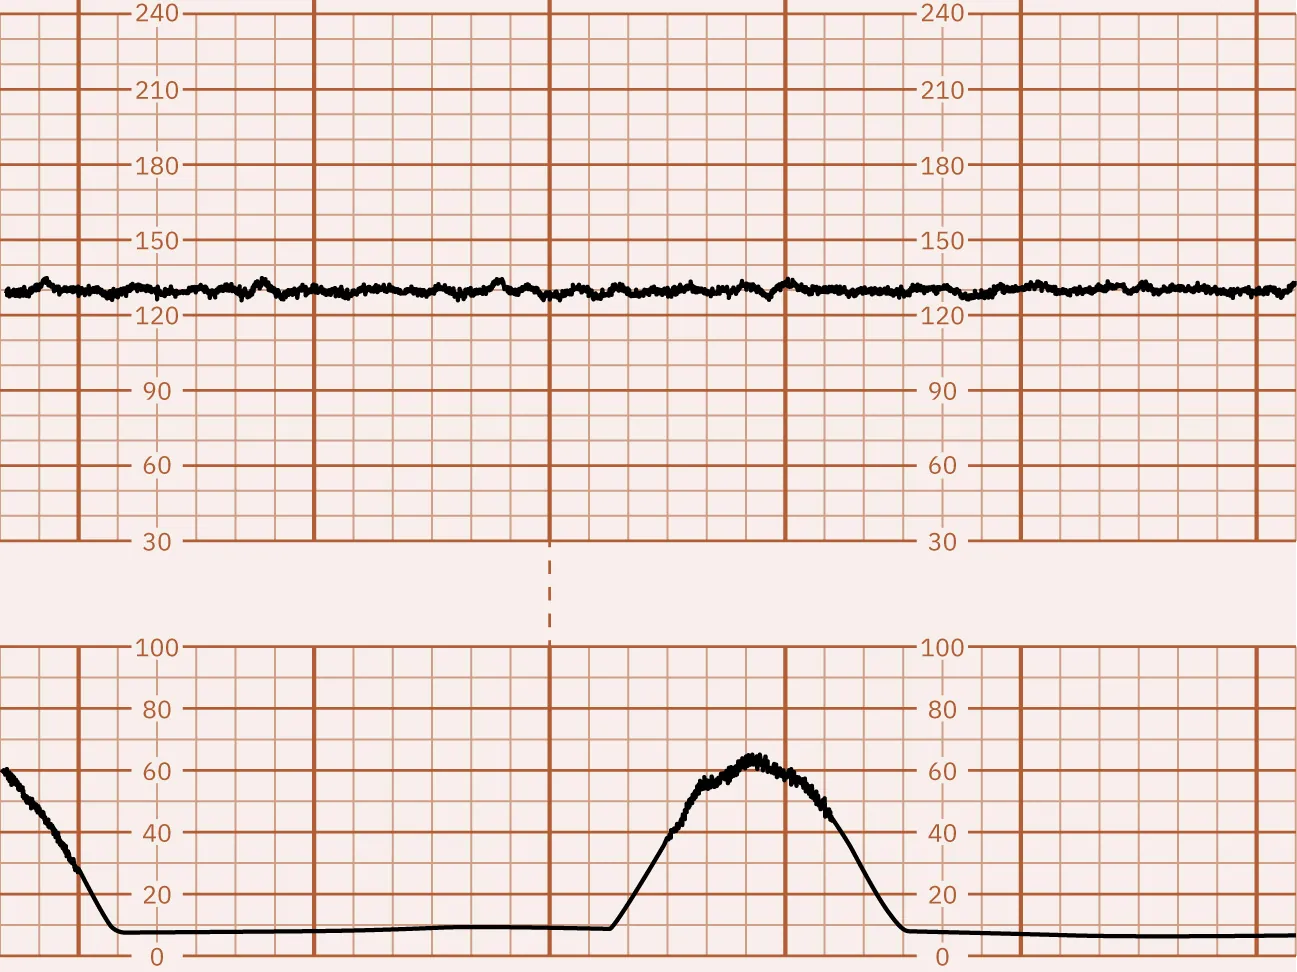

FHR fluctuations of 5 bpm or fewer are considered minimal FHR variability. Minimal variability is associated with fetal acidemia but cannot be the only measure of fetal well-being. Minimal variability can be caused by many factors, such as fetal sleep cycles, fetal anomalies of the CNS, and medications administered to the pregnant patient. Preterm gestation and magnesium sulfate treatment are associated with minimal FHR variability. Figure 16.6 shows a monitor tracing that indicates minimal FHR variability.

Fetal heart rate reading indicating minimal variability.

Figure 16.6 FHR Tracing Indicating Minimal Variability This monitor tracing shows minimal FHR variability with fewer than 5 bpm. (attribution: Copyright Rice University, OpenStax, under CC BY 4.0 license)